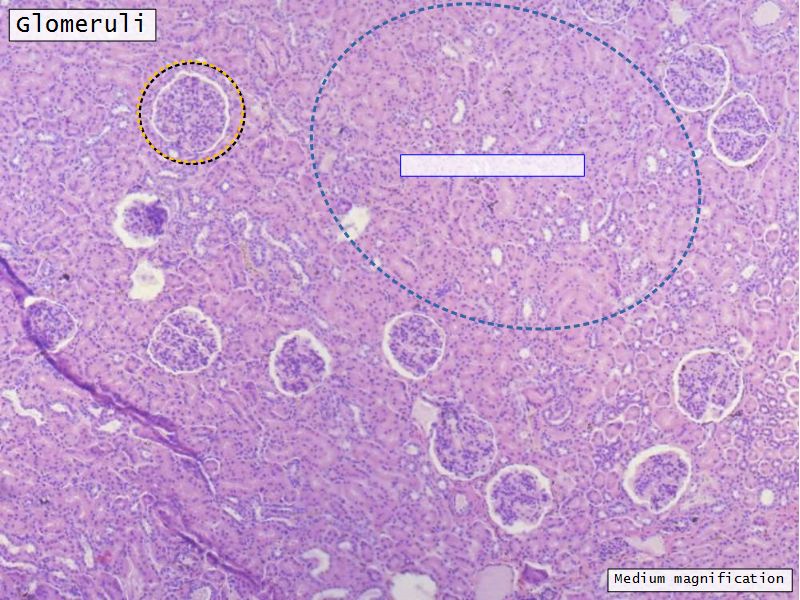

Appearance

- Cortex

- Renal corpuscles

- Convoluted tubules

Kidney lobule

- Group of neprons

- Open into branches

- Same collecting duct

- Not clearly demarcated

- Interlobular arteries/veins

Renal corpuscle

- Tuft of capillaries

- grow into

- Blind end of nephron

- Several layers of epithelium

- Two sides

- Vascular pole

- Tubular pole